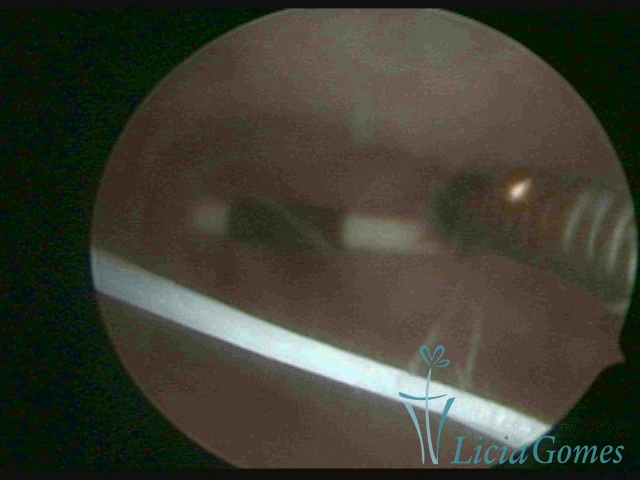

Myometrium punctured IUD

×